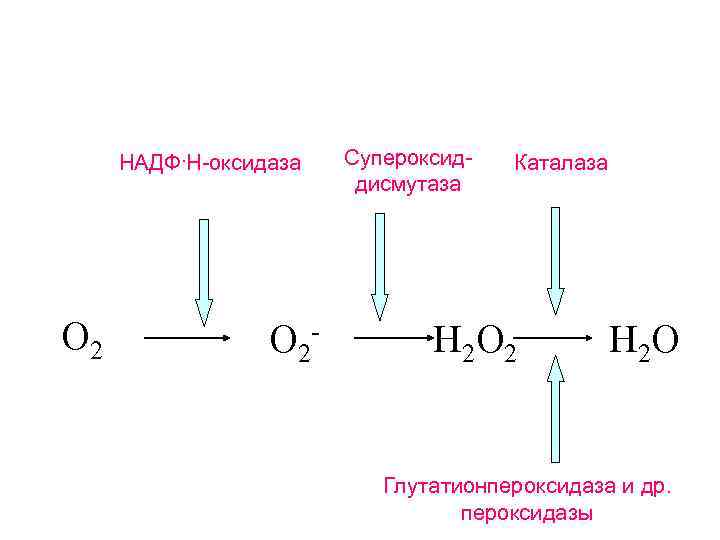

Каким образом фагоцитирующие клетки уничтожают гельминтов? Кислородзависимые механизмы

НАДФ. Н-оксидаза O 2 - Супероксиддисмутаза Каталаза H 2 O 2 H 2 O Глутатионпероксидаза и др. пероксидазы